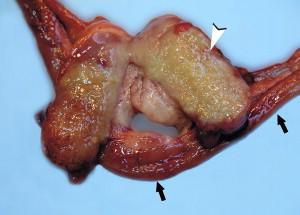

A novel coronavirus of ferrets was first described in 1993. This coronavirus caused an enteric disease called epizootic catarrhal enteritis (ECE). Recently, a ferret systemic coronavirus (FRSCV)-associated disease was discovered. This new systemic disease resembles the dry form of feline infectious peritonitis (FIP) and has been reported in the United States and Europe. This article addresses the clinical signs, pathology, pathogenesis, diagnosis, treatment, and prevention of this ferret FIP-like disease.

1993年首次描述了一种雪貂新型冠状病毒。这种冠状病毒引起了一种称为流行性卡他性肠炎(ECE)的肠道疾病。最近,发现了一种与雪貂全身性冠状病毒(FRSCV)相关的疾病。这种新的全身性疾病类似于猫传染性腹膜炎(FIP)的干性形式,已在美国和欧洲报道。本文阐述了这种雪貂类FIP疾病的临床症状、病理学、发病机制、诊断、治疗和预防。